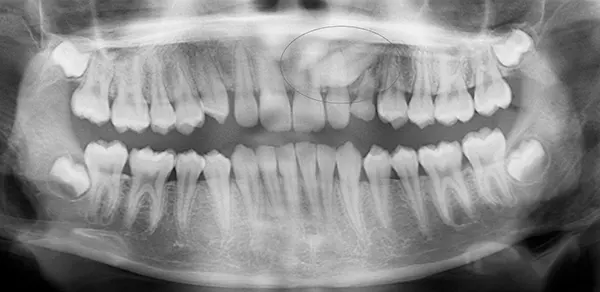

Impacted wisdom teeth can also damage surrounding teeth and jaw structures. Their position makes them difficult to clean, allowing bacteria to accumulate and increasing the risk of infection and decay. For these reasons, removal is often recommended to prevent more serious complications. Routine X-rays during dental exams can help determine whether extraction is necessary.

Wisdom tooth extraction is a common surgical procedure used to remove one or more third molars. It is often recommended to relieve pain, prevent infection, or address overcrowding.

The procedure typically takes about an hour and is performed under local anesthesia or sedation to ensure comfort. During the procedure, our doctor will may make small incisions to safely remove the teeth.